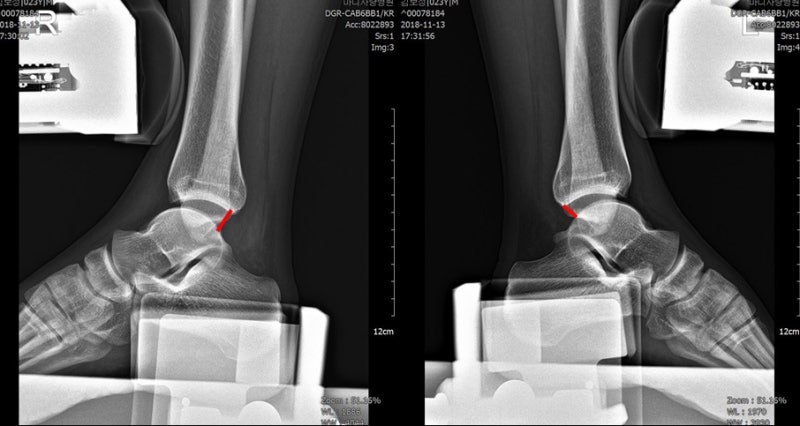

발목 인대 파열(발목 염좌)이란? 발목 인대파열은 발목의 뼈를 연결하는 인대가 손상되거나 늘어나거나 찢어지는 상태입니다. 시간이 지남에 따라 발목 염좌로 인한 통증이 줄어들면서 나아지고 있다고 생각할 수 있습니다. 안타깝게도 인대가 파열되어 발목 인대가 스스로 치유하기가 매우 어렵습니다. 파열된 발복인대에 대한 치료기간을 놓치면 ‘만성 발목 불안정성’이 발생할 수 있으며, 이런 경우 발목 같은 부위에 지속적인 염좌 증상이 나타날 수 있다. 발목 인대 파열 원인 발목을 지지하는 인대가 손상되면 발생합니다. 발목 염좌는 발목에 부담을 주는 격렬한 운동이나 보행 중 발목을 비틀거나 삔 경우에 발생할 수 있습니다. 여성의 경우 하이힐을 신고 걷는 것도 발목 인대 파열을 유발할 수 있습니다. 이 질병의 이름을 들으면 대중을 멀리하는 것처럼 보일 수 있지만 소소한 일상적인 사건이 원인일 수 있습니다. 발목 인대 파열 증상은? 발목 염좌의 가장 흔한 증상은 통증입니다. 통증은 발목뼈에 발생하며 손가락으로 눌렀을 때 압통이 있으며 통증은 간헐적이거나 지속적이다. 손상에 따라 동반 손상이 있을 경우 발목 바깥쪽이나 안쪽에 통증이 있을 수 있으며, 심한 발목 염좌의 경우에는 발목에 타박상이나 타박상과 같은 증상이 나타날 수 있습니다. 발목 인대 파열의 정도에 따라 인대 손상 정도에 따라 1도, 2도, 3도로 나눌 수 있으며 그에 따른 맞춤 치료를 진행하게 됩니다. – 1도 발목 염좌 인대 섬유가 약간 늘어나 약간의 통증, 부종, 관절 강직이 있으며 부상 후 정상적으로 걸을 수 있는 정도를 말합니다. – 인대 섬유의 경미한 찢어짐 및 분리, 중등도의 통증, 부종 및 관절 경직을 동반한 발목 관절의 2도 염좌 부상 후 정상적으로 보행이 불가능하여 보조기가 필요함. – 인대 섬유가 완전히 찢어진 3도 발목 염좌, 매우 심한 통증, 부종 및 관절 경직, 부상 후 체중을 지탱할 수 없는 경우 인대 재건 및 불안정성을 회복하기 위해 수술을 받아야 합니다. 발목인대파열은 어떻게 치료하나 일상생활에 큰 불편함과 통증을 유발하는 질환입니다. 그래도 빠른 치료로 맞춤치료를 진행하는 것이 중요하니 발목을 삐었을 때 어떻게 해야 하는지 알아보도록 하겠습니다. ◎비수술적 발목 염좌의 초기 치료에는 냉찜질, 압박, 고정, 보조기, 목발 사용 등이 있다. 이 치료법은 발목 통증을 완화하고 발목 염좌로 인한 부종을 줄일 수 있습니다. 발목은 보조기나 깁스로 고정한 후 체외 충격파 및 주사 요법을 시행할 수 있습니다. 또한 근력 운동과 균형 운동은 불안정성을 줄여 치유를 도울 수 있습니다. ◎수술적 치료 비수술적 치료로도 증상이 호전되지 않는 경우 수술적 치료를 고려할 수 있습니다. 전거비인대 파열이나 만성 발목 불안정증에 대한 수술적 접근은 크게 해부학적(tenodesis)과 비-해부학적(봉합)으로 나눌 수 있다. 그 중 하지를 함께 강화시키는 변형 브로스트롬 기법이 가장 널리 사용되고 있는데, 변형 브로스트롬 기법의 장점은 기술이 비교적 간단하고 수술 후 발목 관절의 가동 범위를 회복시키며 비골건이나 좌골 신경의 손상을 최소화한다는 점이다. 재활치료 없이 발목 인대 파열 후 초기에는 발목 관절의 양방향 회전을 고정하고 발목 관절만 위아래로 움직이며 발목 관절의 통증이 완화된 후 외근 운동과 내근 운동을 동시에 시행한다. 또한 두발로 서기에서 한발로 서기까지 진행한 후 불안정한 바닥에서 한발 그립으로 재활방법을 시행하는 근력운동도 병행할 수 있다. 발목 인대 파열은 일상생활에서 경미한 사건일 수 있습니다. 어떻게 보면 사소할 수도 있지만 이러한 증상은 일상생활을 힘들고 고통스럽게 만들 수 있습니다. 발목에 통증이 느껴지지만 인지하지 못한다면 즉시 병원을 찾아 정확한 치료를 받아야 합니다. 광고 후에 계속하십시오. 다음 주제작가 취소 발목 인대 파열 참지 마세요 재생 10 좋아요 5 좋아요 공유 0:00:00 재생 음소거 00:00 00:25 라이브 전체 화면 해상도 설정 자동 480p 자막 재생 속도 비활성화 1.0x(기본) 해상도 자동(480p) 720p HD 480p 360p 270p 144p 자막 설정 비활성화 옵션 텍스트 크기 배경색 재생 속도 0.5 x 1. 0x(기본값) 1.5x 2.0x 알 수 없는 오류가 발생했습니다. 도움말 보기 음소거되었습니다. HD로 재생하려면 이 동영상에 라이선스를 부여하세요. 설정에서 해상도를 변경해 보세요. 자세히 알아보기 0:00:00 Collapse/Expand발목 인대 파열은 참을 수 없다발목 인대 파열은 참을 수 없다 #광고발목 인대 파열이 계속된 후. 다음 주제작가는 발목 인대 파열을 취소하고 더 ​​이상 복용하지 않습니다. 배경색 재생 속도 0.5x 1. 0x(기본값) 1.5x 2.0x 알 수 없는 오류가 발생했습니다. 도움말 보기 음소거되었습니다. HD로 재생하려면 이 동영상에 라이선스를 부여하세요. 설정에서 해상도를 변경해 보세요. 자세히 알아보기 0:00:00 Collapse/Expand발목 인대 파열은 참을 수 없다발목 인대 파열은 참을 수 없다 #광고발목 인대 파열이 계속된 후. 다음 주제작가는 발목 인대 파열을 취소하고 더 ​​이상 복용하지 마십시오. 재생 좋아요 5개 좋아요 5개공유 0:00:00 재생 음소거 00:00 00:05 라이브 전체 화면 해상도 설정 자동 480p 자막 비활성화 재생 속도 1.0x(기본값) 해상도 자동(480p) 720p HD 480p 360p 270p 144p 자막 설정 비활성화 텍스트 크기 배경색 재생 속도 0.5x 1. 0x(기본값) 1.5x 2.0x 알 수 없는 오류가 발생했습니다. 도움말 보기 음소거되었습니다. HD로 재생하려면 이 동영상에 라이선스를 부여하세요. 설정에서 해상도를 변경해 보세요. 자세히 알아보기 0:00:00 Collapse/Expand발목 인대 파열은 참을 수 없다발목 인대 파열은 참을 수 없다 #광고발목 인대 파열이 계속된 후. 다음 주제작가 취소 발목 인대 파열 참지 마세요 재생 7 좋아요 5 좋아요 공유 0:00:00 재생 음소거 00:00 00:05 라이브 전체 화면 해상도 설정 자동 480p 자막 비활성화 재생 속도 1.0x(기본값) 해상도 자동(480p) 720p HD 480p 360p 270p 144p 자막 설정 비활성화 옵션 텍스트 크기 배경 컬러 재생 속도 0.5x 1.0x(기본값) 1.5x 2.0x 알 수 없는 오류가 발생했습니다. 도움말 보기 음소거되었습니다. HD로 재생하려면 이 동영상에 라이선스를 부여하세요. 설정에서 해상도를 변경해 보세요. 자세히 알아보기 0:00:00 Collapse/Expand발목 인대 파열은 참을 수 없다발목 인대 파열은 참을 수 없다 #광고발목 인대 파열이 계속된 후. 다음 주제작가는 발목 인대 파열을 취소하고 더 ​​이상 복용하지 않습니다. 배경색 재생 속도 0.5x 1. 0x(기본값) 1.5x 2.0x 알 수 없는 오류가 발생했습니다. 도움말 보기 음소거되었습니다. HD로 재생하려면 이 동영상에 라이선스를 부여하세요. 설정에서 해상도를 변경해 보세요.더 알아보기 0:00:00 접히다 펴다 발목인대파열 참지못해 발목인대파열 참지못해 #AnkleLigamentTears